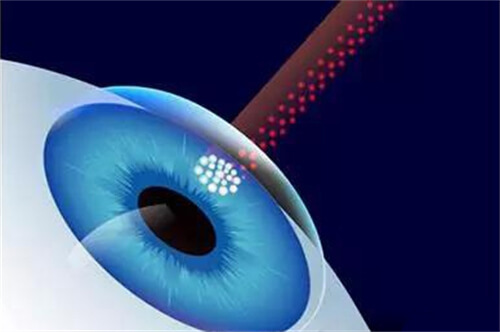

手术费用涵盖超声乳化技术、飞秒激光辅助等选项。

通过***光线追踪模拟,优化晶体前表面曲率,实现焦深延长。